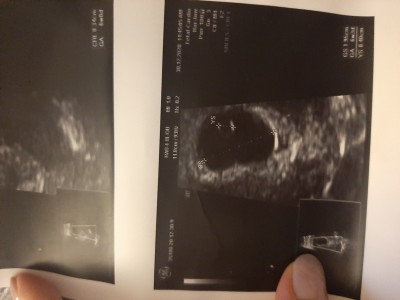

Bugün ilkkez ultrasona girdim son adet tarihim 20aralik 5+5 brbek gözükmedi bos gebelik de olabilir dedi gec dollenmede küçük olduğundan da olabilir dedi zaten korkuyodum boş gebelik olmasindan öyle deyince cok üzüldüm eve geldiğimde saatlerce ağladım saglikli bi kese olup olmadığında söylemedi ama yolk kesesi olusmus

Gebelik haftası 5+5

Yolk kesesi oluşursa eğer boş gebelik olma ihtimali ortadan kalkıyor. Yolk kesesi bebeğin oluşacağınin habercisidir. Lütfen ağlama üzme kendini kesenin ici dolu bak ben resim yuklicem şimdi bana da boş gebelik dediler ama resme bakınca anlarsın bomboş hiç bişey yok içinde. 8. Hafta bebeğide gördük kalp atışını da çok şükür. Bol bol dua et senin kesen boş kese değil Allah'ın izni ile. ♥️

Yok canım korkma hemen boş gebelik demek için çok erken yolk kesende oluşmuş kesende gayet düzgün görünüyor bebeğin gözükmesine daha zaman var henüz geç döllenmede olabilir dediği gibi bir sonraki muayenede gözükebilir bidaha ne zaman çağırdı

Canım yolk kesen oluşmuş boş gebelik olmaz bu. Benim sağlıksız gebelik olduğu halde yolktan sonra bebeği gördüm. Sıkma canını güzel düşün güzel olsun <3

Canım bebegi görmek için erken zaten nadir olur bebeğin gözükmesi 5 haftada sakin uzme kendini gayet güzel duruyor benim de böyleydi ilk gittiğimde iyi bisey degil ama doktorlar maalesef hemen yapıştırıyor boş gebelik kimyasal gebelik fln diye icin rahat olsun haftaya baska doktora git bekleyemezsen en azından 3 4 gun bekle öyle git Allahın izniyle bisey olmaz icin ferah olsun bak foto attım benim 6+3 ultrason görüntüsü hala bebek yoktu